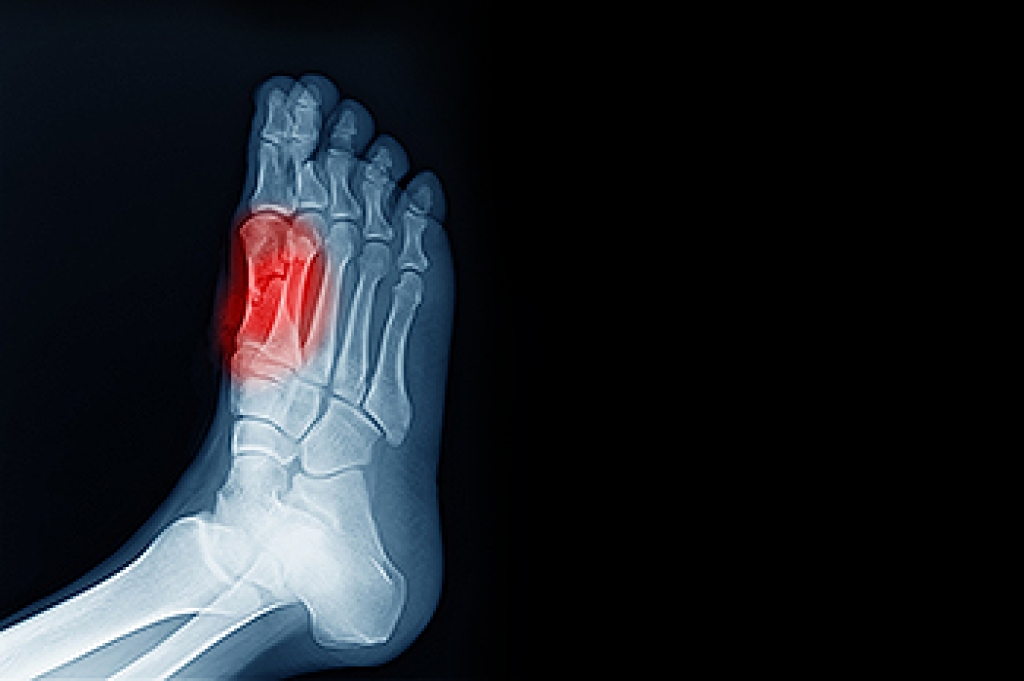

Hammertoe is a foot deformity that affects the joints of the second, third, fourth, or fifth toes of your feet. It is a painful foot condition in which these toes curl and arch up, which can often lead to pain when wearing footwear.